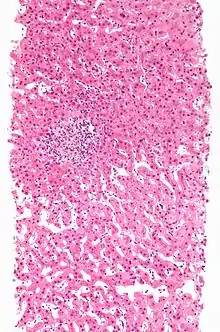

Adverse drug reaction leading to hepatitis (drug-induced hepatitis) with granulomata. Other causes were excluded with extensive investigations. Liver biopsy. H&E stain.